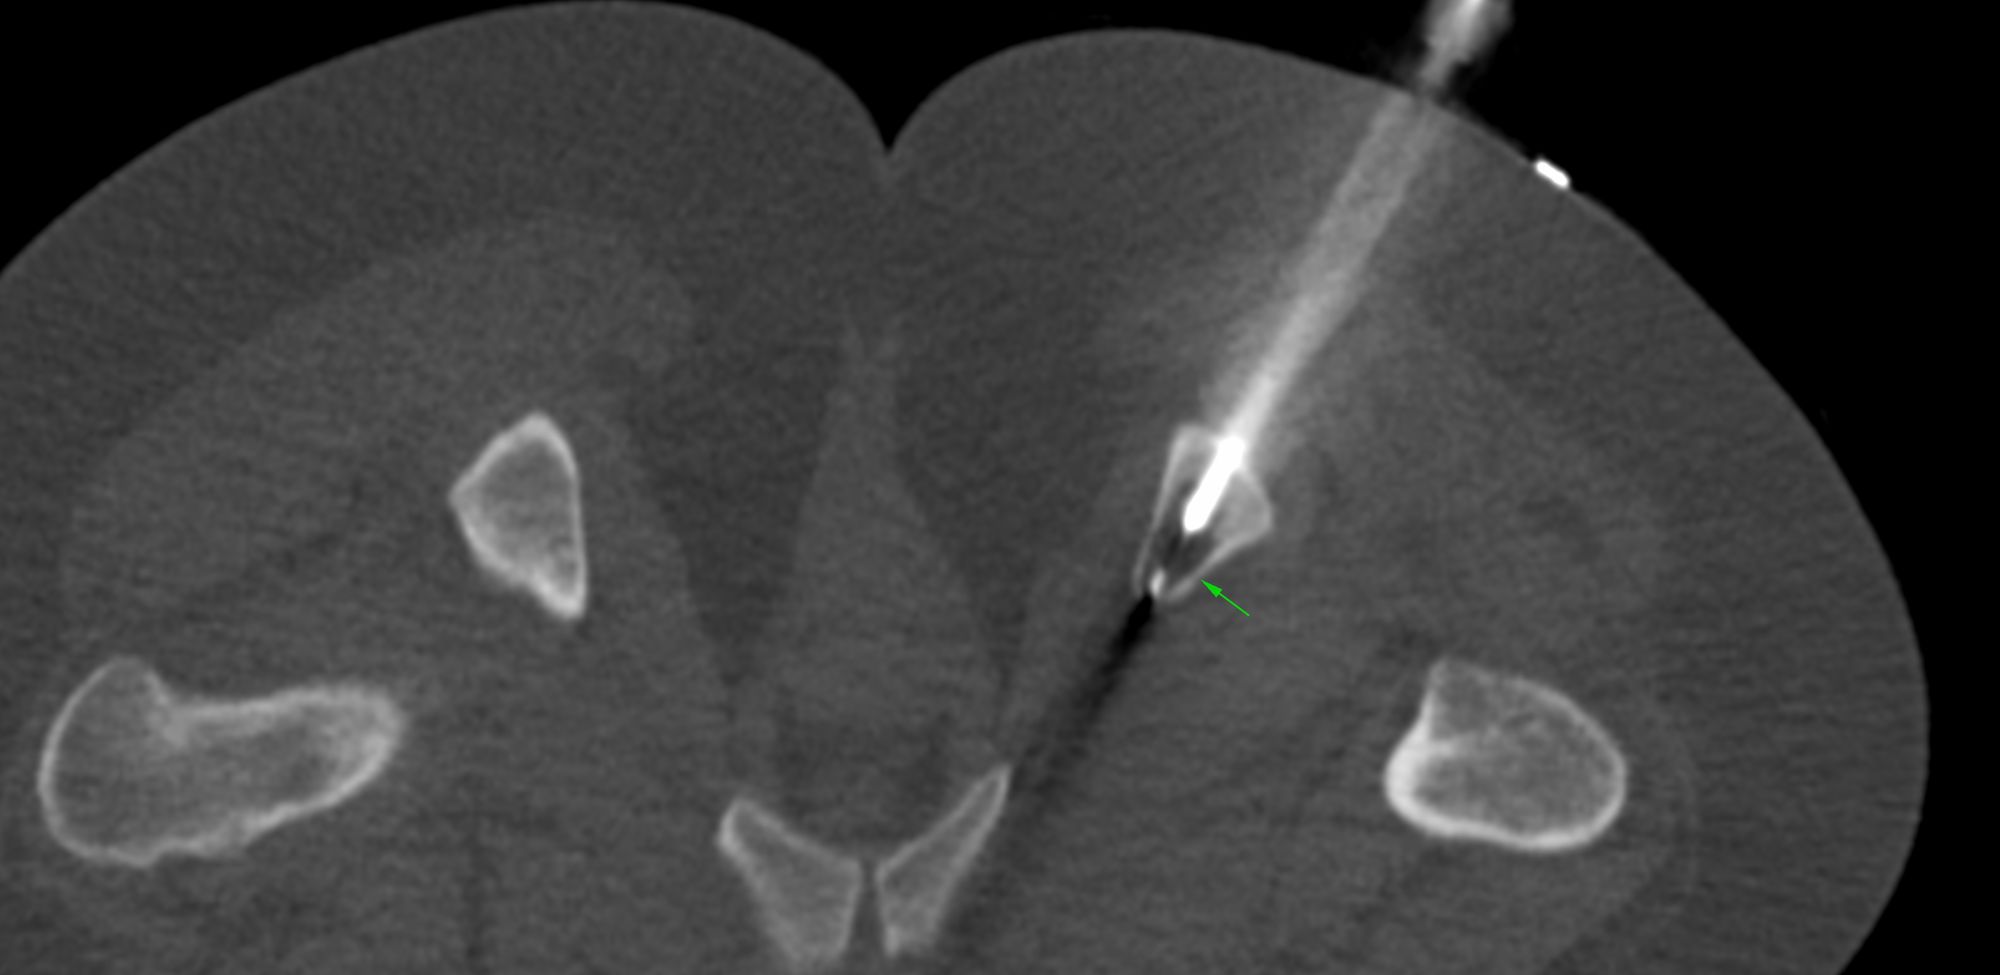

Case 11: D3 Spinal Transverse Process and Pedicle Biopsy

Bhavin Jankharia - 10 March 2021